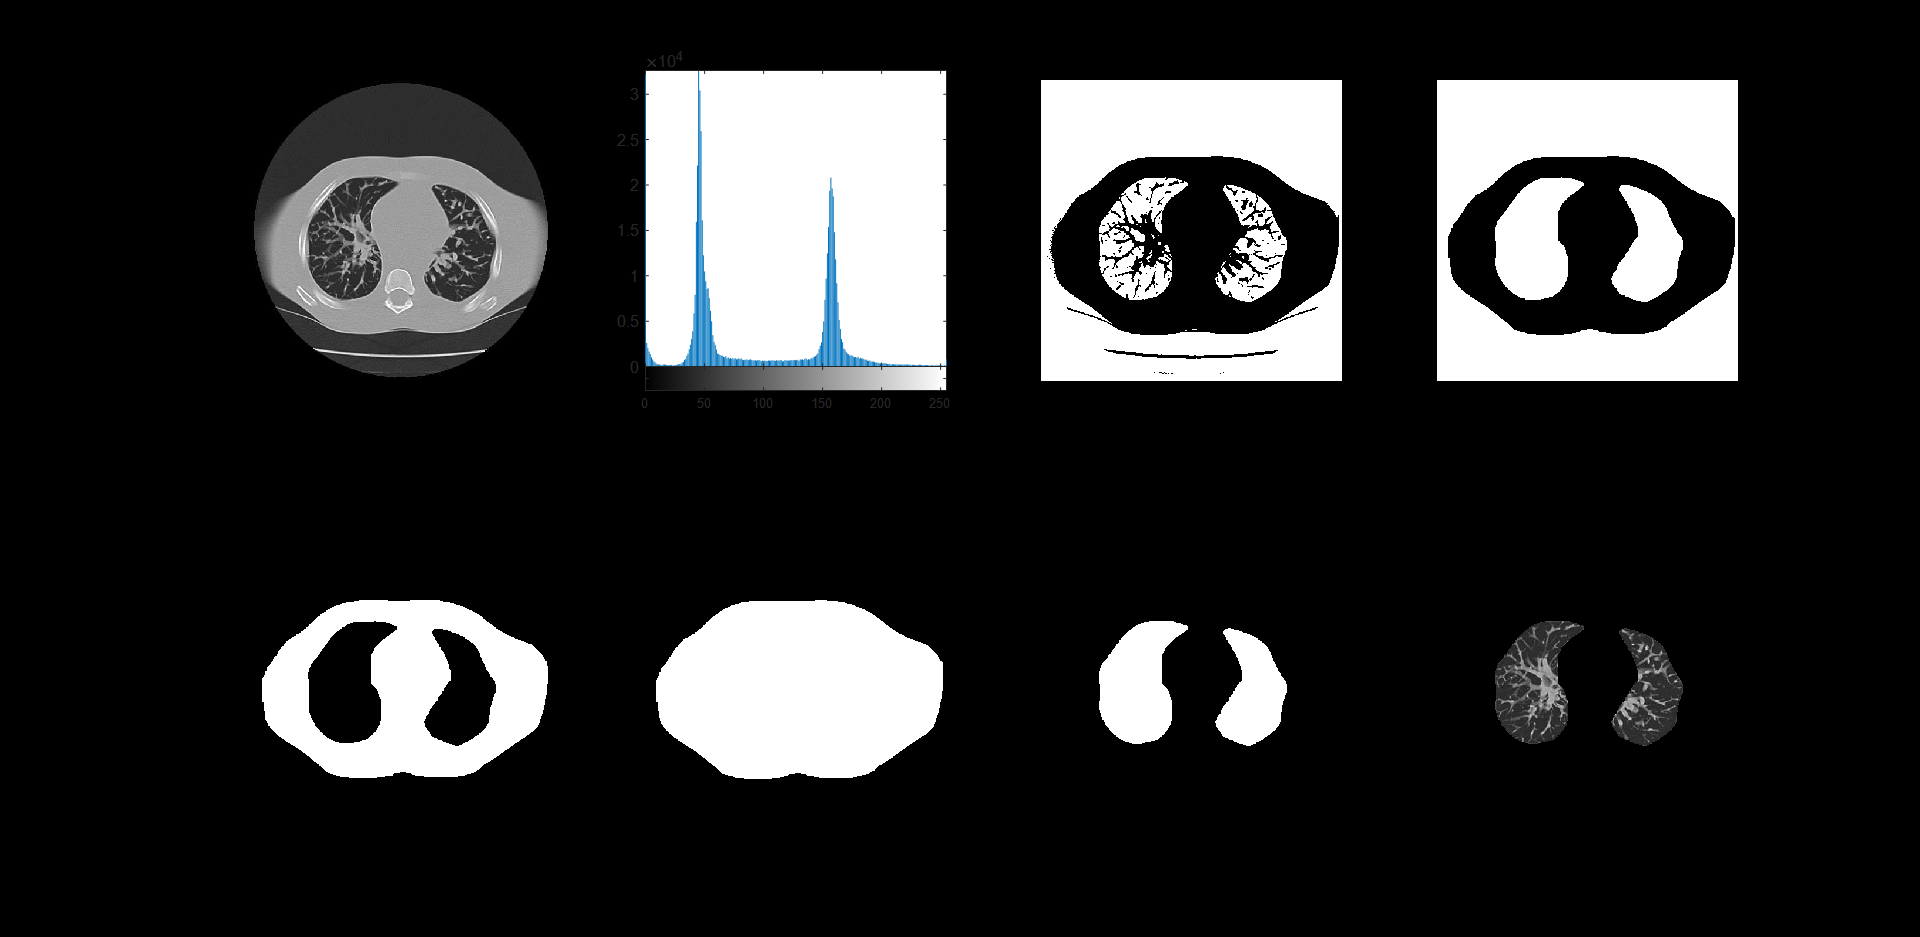

- 肺实质提取

提取肺实质算法流程如下:

(1)基于全局阈值的分割

(2)执行取反操作

(3)应用半径为13的标准圆形结构单元进行闭运算

(4)再次执行取反操作

(5)完成孔洞填充处理

(6)进行掩膜与原图的差集运算

(7)通过掩膜与原图的乘法获得最终肺实质图像

subplot(243);imshow(g1),title('二值图像');

se2 = strel('disk',17); % 半径为17的圆形结构元

image2 = imclose(g1,se2);

subplot(2,4,4); imshow(image2); title('经半径为17的圆形结构元闭运算');

tI=~image2;%取反

subplot(2,4,5); imshow(tI); title('取反');

img_fill = imfill(tI, 'holes');

subplot(246),imshow(img_fill), title('孔洞被填充的图像');

img_jian=img_fill-tI;

subplot(247),imshow(img_jian), title('模板');

subplot(248),imshow(lung), title('肺实质');

分割效果